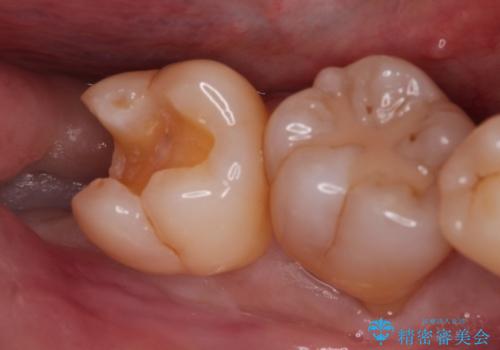

親知らずが原因の深いむし歯

- 検診にて親知らずが原因と思われる深いむし歯を発見し、親知らずを抜歯した後ゴールドインレーにて修復治療を行っております。

ゴールドインレーにて修復を行うことで適合の良い治療を行うことができました。